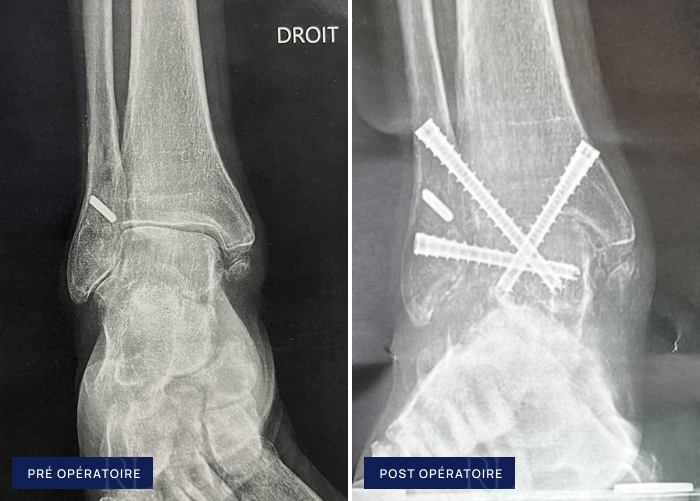

Avant après Arthrose de cheville

Radiographies pré et post opératoire d’arthrose de cheville

À gauche : Usure globale du cartilage de la cheville (arthrose tibio talienne)

À droite : Arthrodèse de cheville (triple vissage percutané)